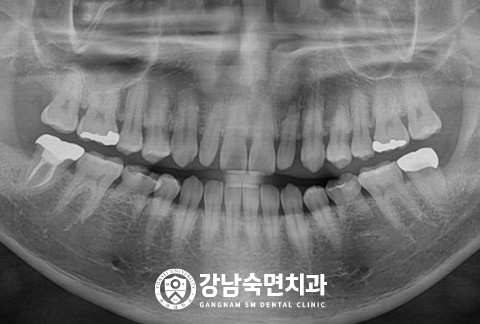

임플란트-보철-시-기성-어버트먼트가-아닌-맞춤-지대주-사용-보철-파절-위험-방지-음식물-끼임-방지-주위염-방지-맞춤-지대주는-환자의-구강환경에-맞는-교합을-구현할-수-있고-앞니-보철시-더욱-심미적으로-제작이-가능합니다

임플란트-전후사진